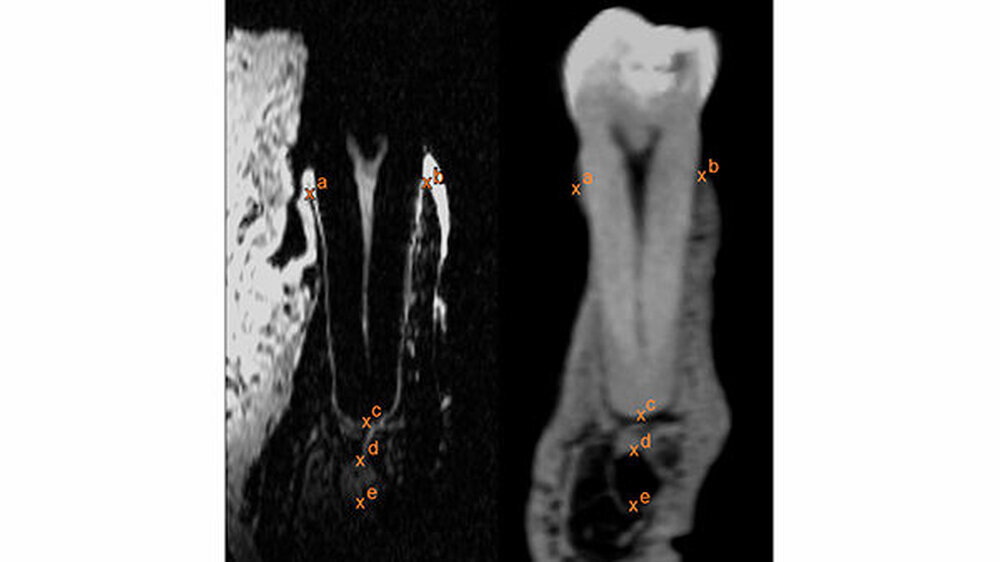

Kieferknochen, Gefäß-Nerven-Stränge und das Weichgewebe werden dargestellt

„Die neue Methode trägt wesentlich dazu bei, dass die Magnetresonanztomografie in Zukunft die konventionelle Röntgendiagnostik in der Zahn-, Mund- und Kieferheilkunde ersetzen wird“, sagt Oberärztin Prof. Katja Nelson. „Vor einer Operation können wir Kieferknochen, Gefäß-Nerven-Stränge und das umgebende Weichgewebe darstellen und so bei der Operation besonders schonend vorgehen, ohne den Nerv zu treffen.“ Da für die Patienten keine Strahlenbelastung besteht, könnten Ärzte die Bildgebung auch erstmals zur regelmäßigen Kontrolle des Heilungsverlaufs einsetzen.

Kernstück der Dental-MRT-Methode ist eine etwa einen Zentimeter hohe Spule aus zwei parallel angeordneten Metallringen. Aufgrund ihrer elektrophysikalischen Eigenschaften verstärkt die Doppelspule die MRT-Signale des umschlossenen Gewebes. Dadurch wird eine Auflösungsgenauigkeit von etwa einem Drittel Millimeter erreicht, die der des Röntgens nahekommt. Die Spule funktioniert ohne Energie und ist für den Patienten absolut ungefährlich. „Unsere Lösung für ein altes Problem der Zahnheilkunde ist an sich technisch recht einfach und trotzdem eine echte Innovation“, sagt Studienleiter Jan-Bernd Hövener.

Mithilfe der entwickelten drahtlosen, intraoralen, induktiv-gekoppelten Spulen kann demnach ein MRT in einer ausgewählten Region mit hoher Auflösung in einer klinisch möglichen Zeit von etwa vier Minuten erstellt werden. In der Vergangenheit wurde den Forschern zufolge schon versucht, das MRT-Signal mit Einzelspulen zu verstärken, allerdings ohne durchschlagenden Erfolg. Die jetzt verwendete Doppelspule erlaube nun Bilder von wesentlich höherer Qualität. Dass die Spule kein Kabel benötigt, erleichtere zudem den Einsatz für den Patienten. Die Freiburger Forscher haben die neue Methode bereits patentieren lassen.